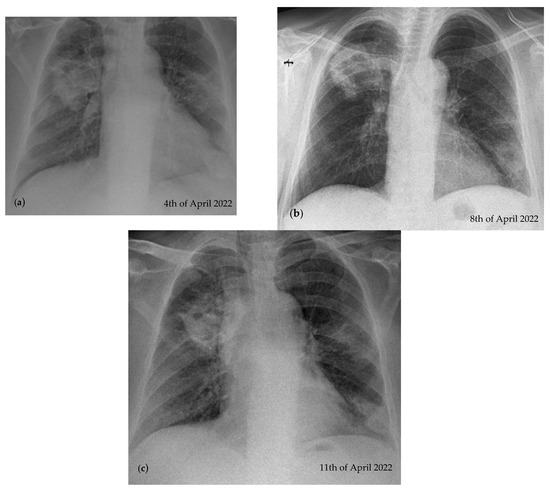

2.2. Blood Workup, Functional Tests, Bronchoscopy, and Radiological Findings

2.3. Treatment and Monitoring

2.4. Follow-Ups